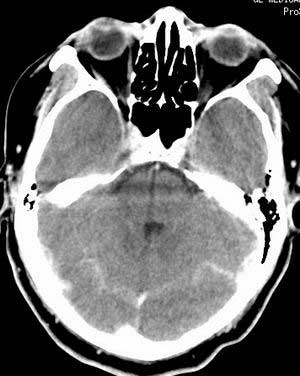

增强扫描:

脑实质密度均匀,未见异常密度灶,脑沟裂池室形态大小正常,中线结构居中.

双侧乳突蜂房密度呈气体样,慢性乳突炎可能性不大,

双侧颞叶脑实质密度均匀未见异常密度灶,

考虑颅内未见异常。

最好能加照ct骨窗,观察右侧岩骨。

建议mr检查可轴、冠、矢多体位,mr 可以发现ct不能发现的许多异常影像。

建议行mr检查排除右枕硬膜下脓肿可能。